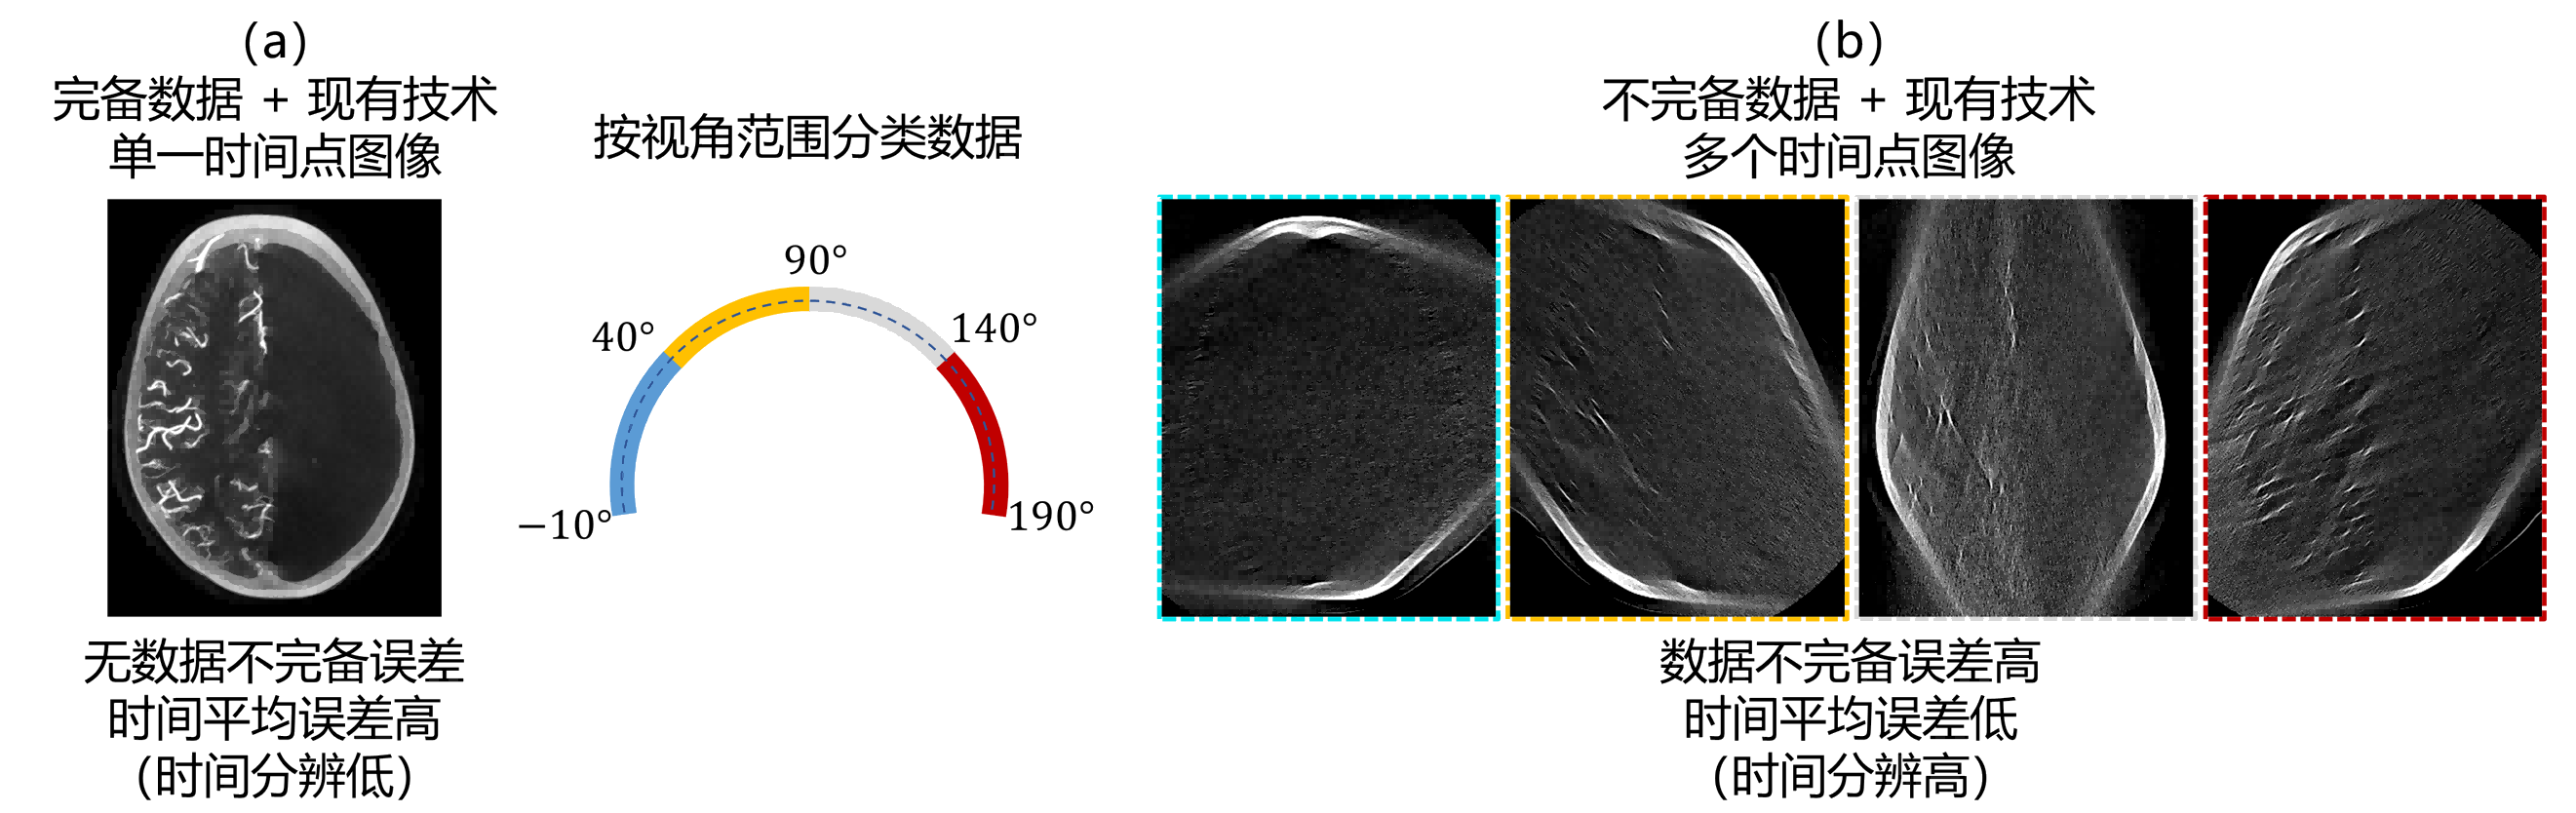

断层图像重建要求被扫物体在采集最小完备数据时间内是静态的。当该要求不被满足时,重建图像具有时间平均误差(即,时间分辨低)。当机架转速固定时,使用较短视角范围数据重建图像,即,提高重建方法的时间分辨,可减小该误差。然而,使用较短视角范围数据重建图像违背数据完备性条件,导致数据不完备误差(如图1所示)。现有方法,包括传统FBP和有限角度重建方法,都无法将这两种误差同时最小化。

图1. (a)完备数据使用现有技术仅能重建单个时间点图像,该图像无数据不完备误差,但时间平均误差高,时间分辨低;(b)按视角范围分类数据,每个数据子集不完备,使用现有技术重建多个时间点图像,每个图像时间平均误差低,时间分辨高,但不完备误差高。